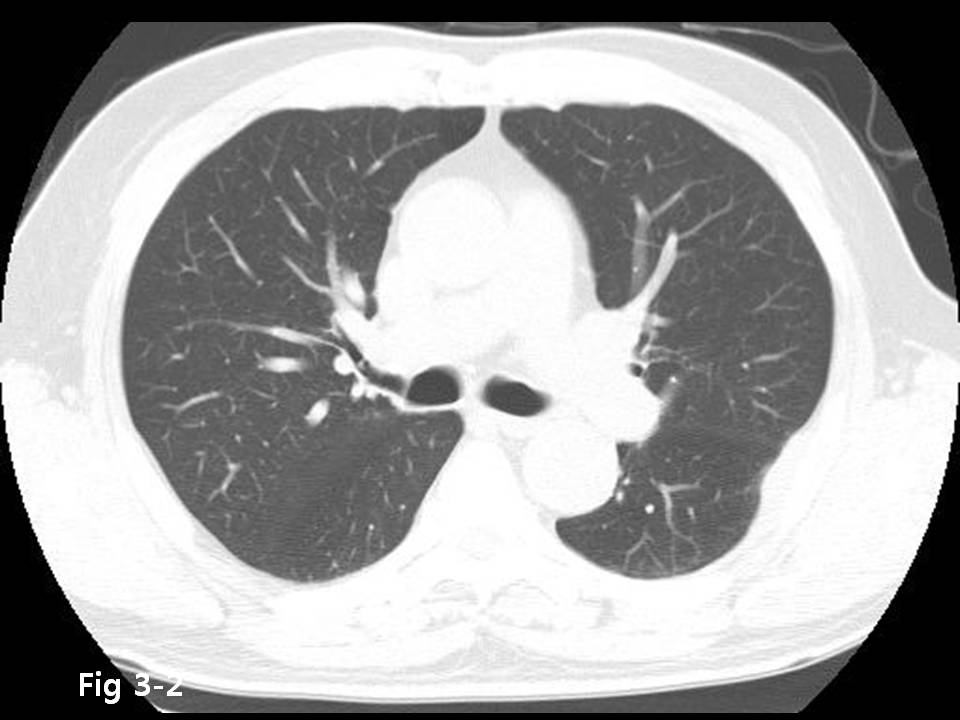

M/70

Chest pain  È£¼Ò

Chest CT ¿Ã·Á ÁÖ¼¼¿ä